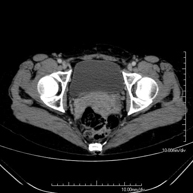

- Pelvis CT

Diagnostic test that involves obtaining high-definition anatomical two- and three-dimensional images of the pelvis (bone structures, vascular structures, bladder, uterus and ovaries, prostate and seminal vesicles, ureters, etc.) using CT (computed tomography) equipment. Most studies require the use of iodinated contrast.